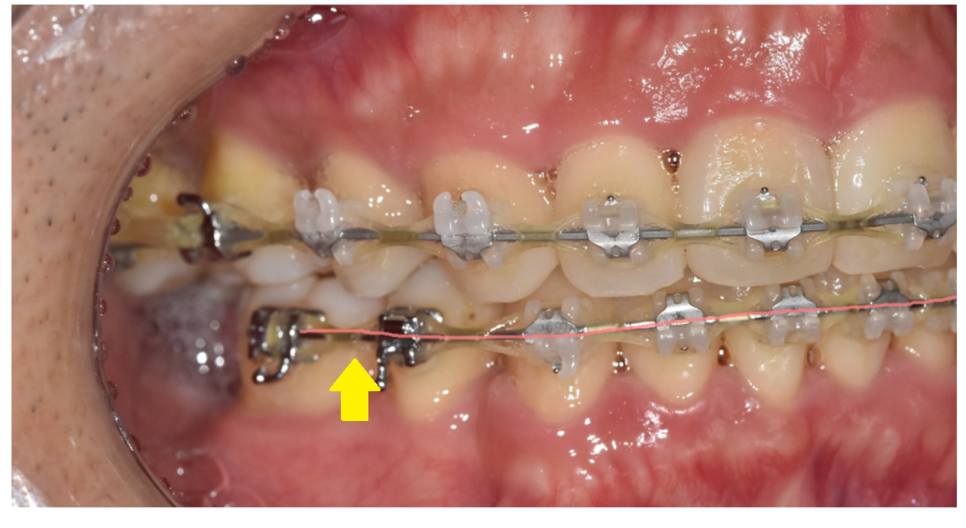

치아에 장치를 붙이는 경우에

철사를 넣어 교정을 진행합니다.

교정 치료에서 철사(와이어)는

브라켓에 연결되어 치아에 지속적인 힘을 가해 움직이게 하는 핵심 부품이에요.

교정 초기와 후반부에 사용하는 와이어 역할이 다릅니다.

교정 중간~후기에는 굵고 단단한 철사를 사용합니다.

강한 힘을 지속적으로 주어

치아의 세밀한 정렬을 도와주죠